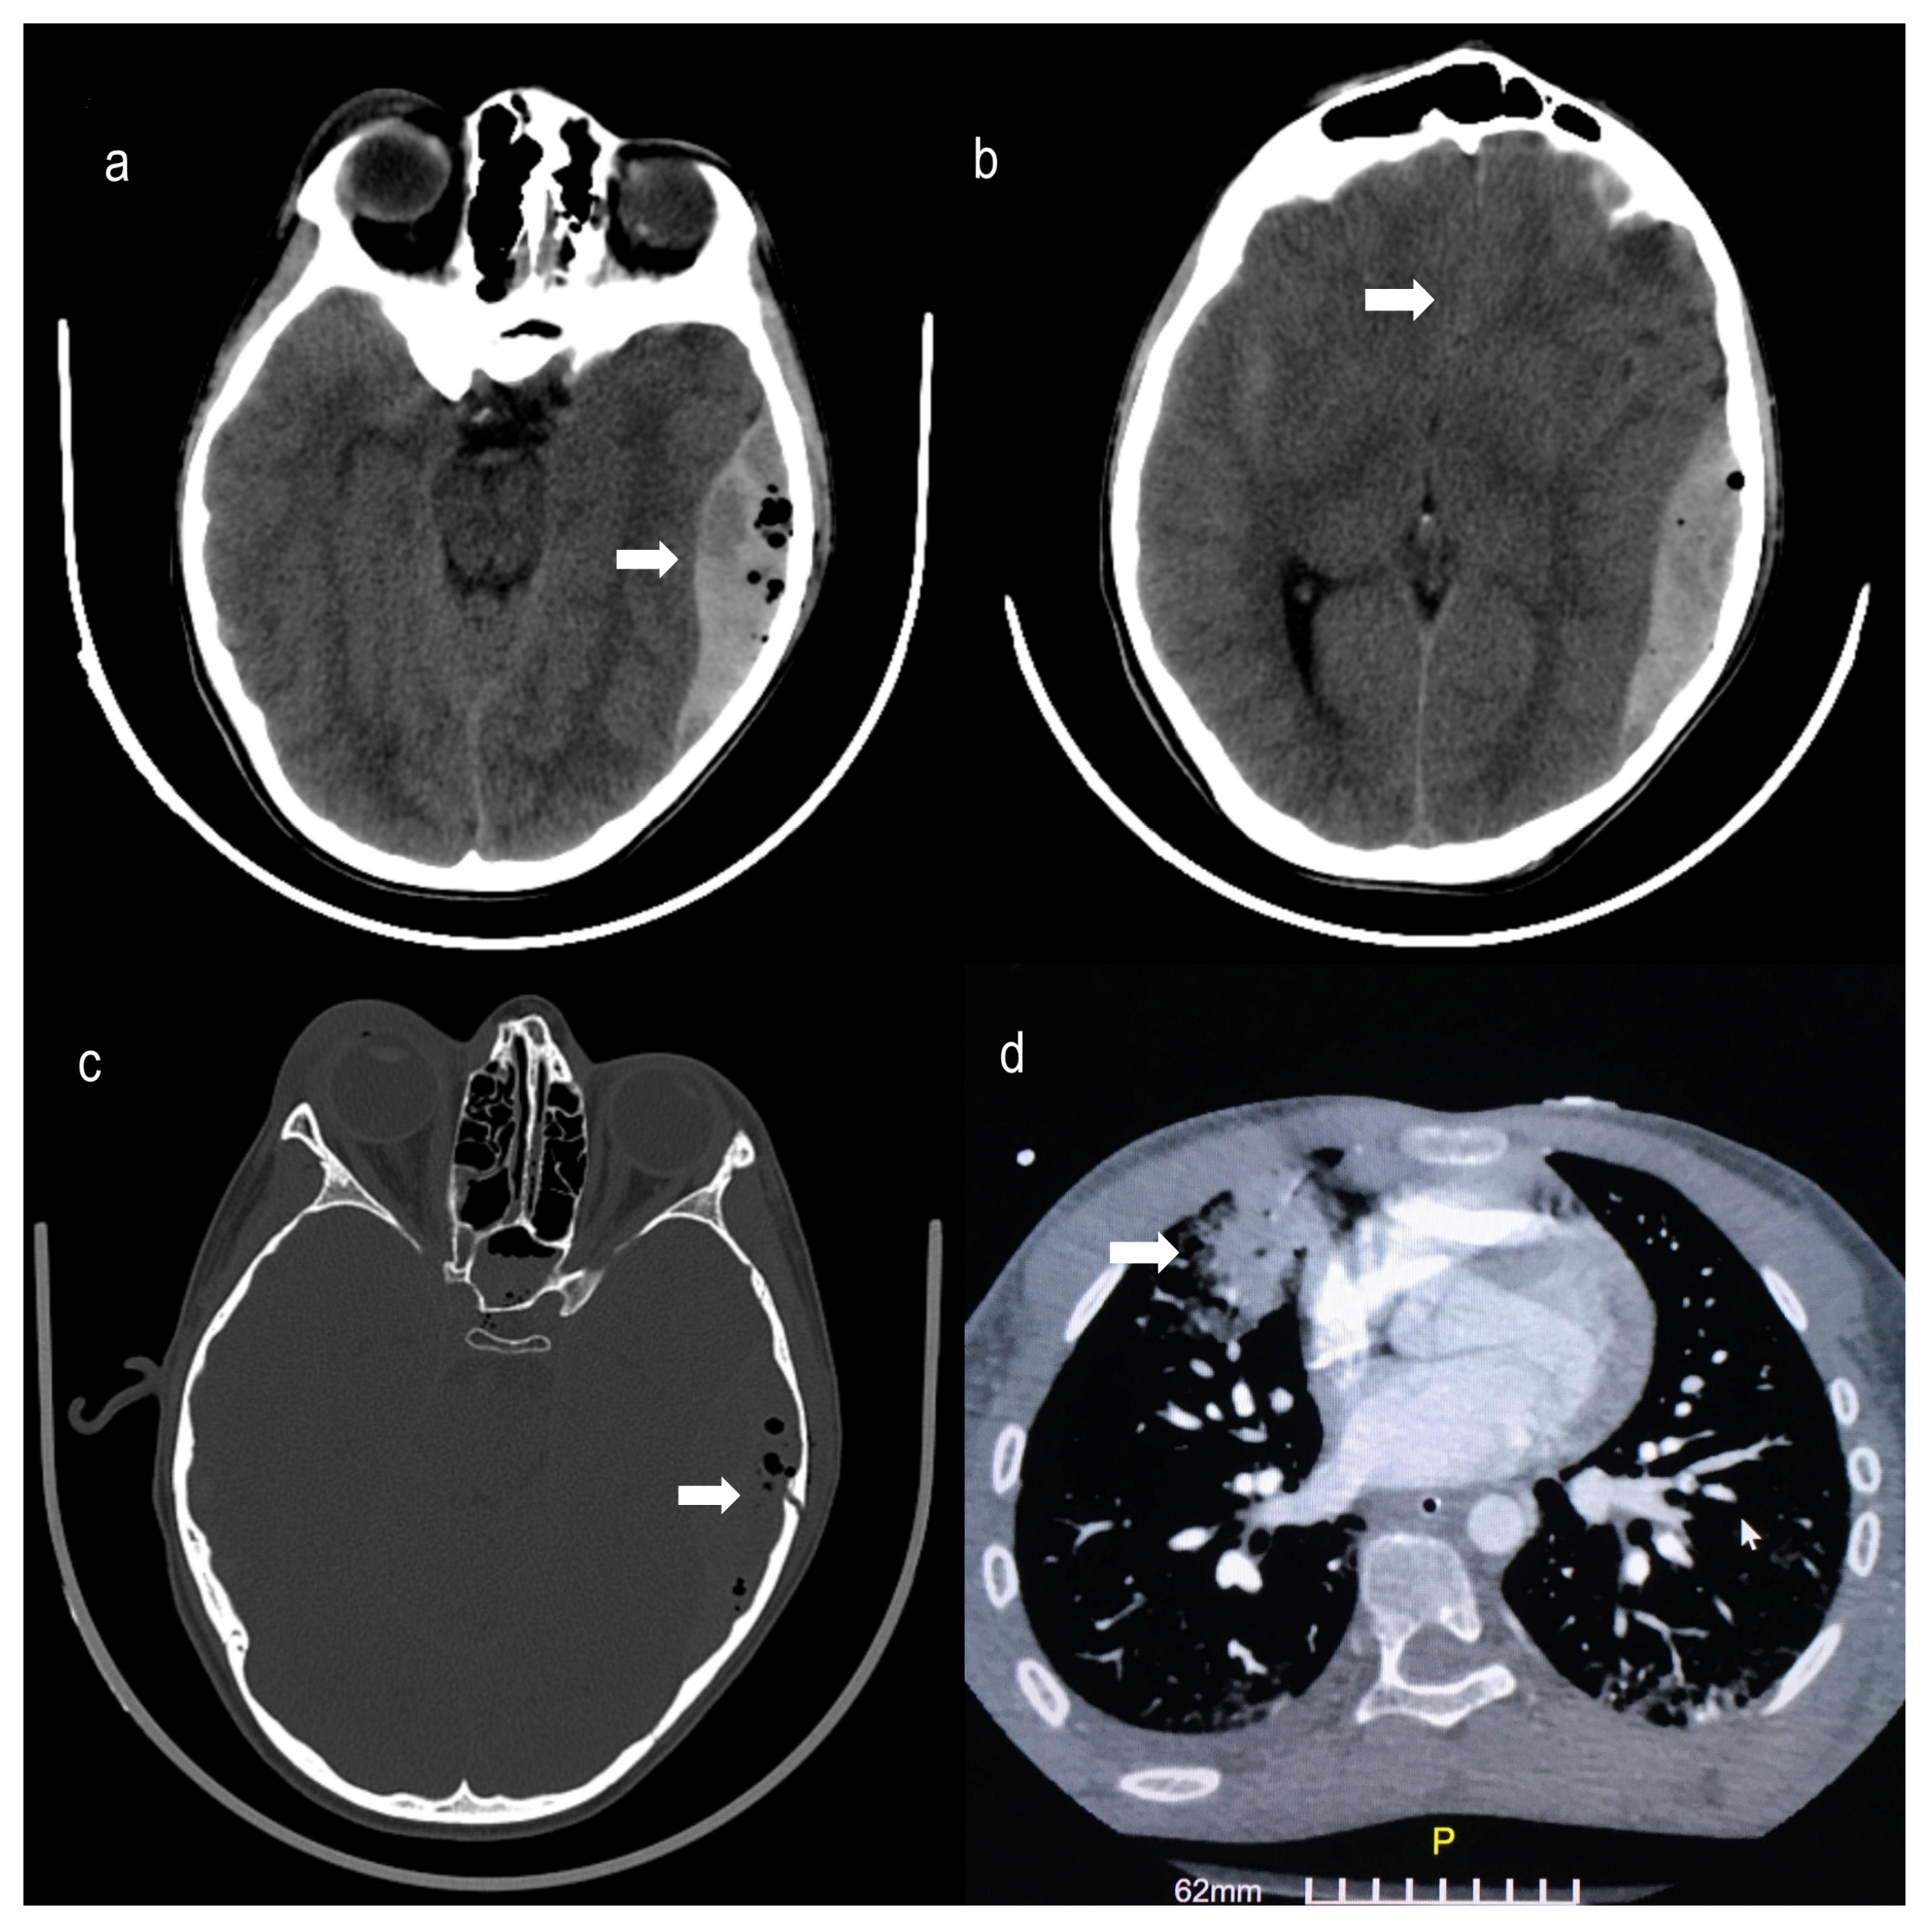

2. Case Presentation